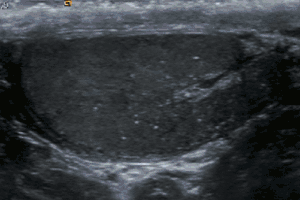

Testicular microlithiasis is an unusual condition diagnosed on testicular ultrasound. It is found in between 1.5 to 5% of normal males, and may be found in up to 20% of individuals with subfertility. It is an asymptomatic, non-progressive disease.

The cause is unknown, but this condition has been associated with testicular cancer in a small group of individuals, cryptorchidism, mumps, infertility and intraepithelial germ cell neoplasia. Classic testicular microlithiasis is defined as five or more echogenic foci per view in either or both testes, and limited testicular microlithiasis defined as one or more echogenic foci that do not satisfy the criteria for classic testicular microlithiasis. In 80% of cases, both testicles are affected.